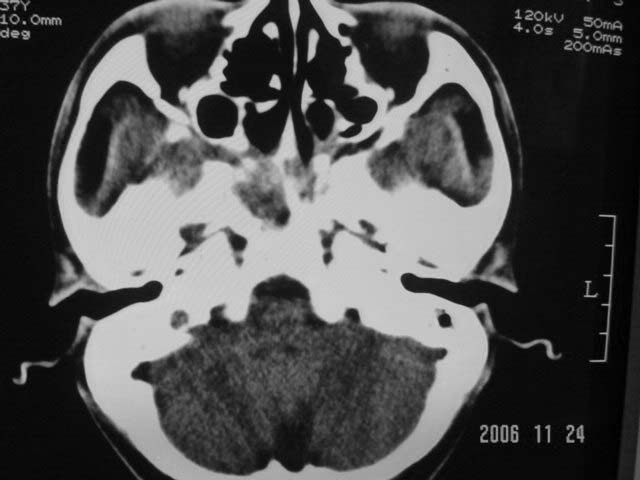

右侧鼻咽部软组织肿块,颅底骨质破坏,右侧颈部淋巴结肿大;诊断:鼻咽ca、右颈部淋巴结转移、颅底侵犯

右侧鼻口咽侧后壁不规则增厚,内可见密度不均匀性椭圆形软组织块影,边界欠清,咽旁间隙尚清.右颈部可见圆形软组织块影,鼻塞、耳鸣3个月,涕中带血2周,颈部可触及肿大淋巴结,考虑鼻咽癌,颈部淋巴转移.

右侧鼻咽后壁不规则增厚,内可见密度不均匀性椭圆形软组织块影,边界欠清,咽旁间隙尚清.右侧下方可见圆形软组织块影,双侧蝶窦呈均一高密度。

考虑:1、右侧鼻咽癌伴颈部淋巴结转移;

2、双侧蝶窦炎。

右侧鼻咽后壁不规则增厚,内可见软组织肿块,右侧颈部淋巴结肿大;双侧蝶窦呈均一高密度。

诊断:鼻咽ca伴右颈部淋巴结转移

双侧蝶窦炎

右侧鼻咽侧后壁不规则增厚,咽隐窝变钝,咽旁间隙变狭窄,见组织结节影[哨兵征],蝶骨似破坏,蝶窦内充塞软组织影,翼内外肌上分间隙模糊,右颈后三角区淋巴结肿大,右侧乳突增高气房消失。考虑鼻咽癌伴蝶窦侵犯及淋巴结转移,右侧浆液性中耳炎。其他恶性病变待排。